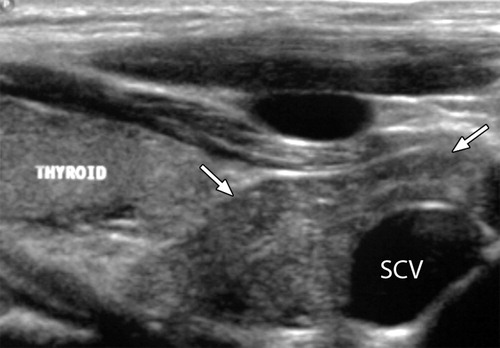

Тимомегалия: что это такое и как проявляется